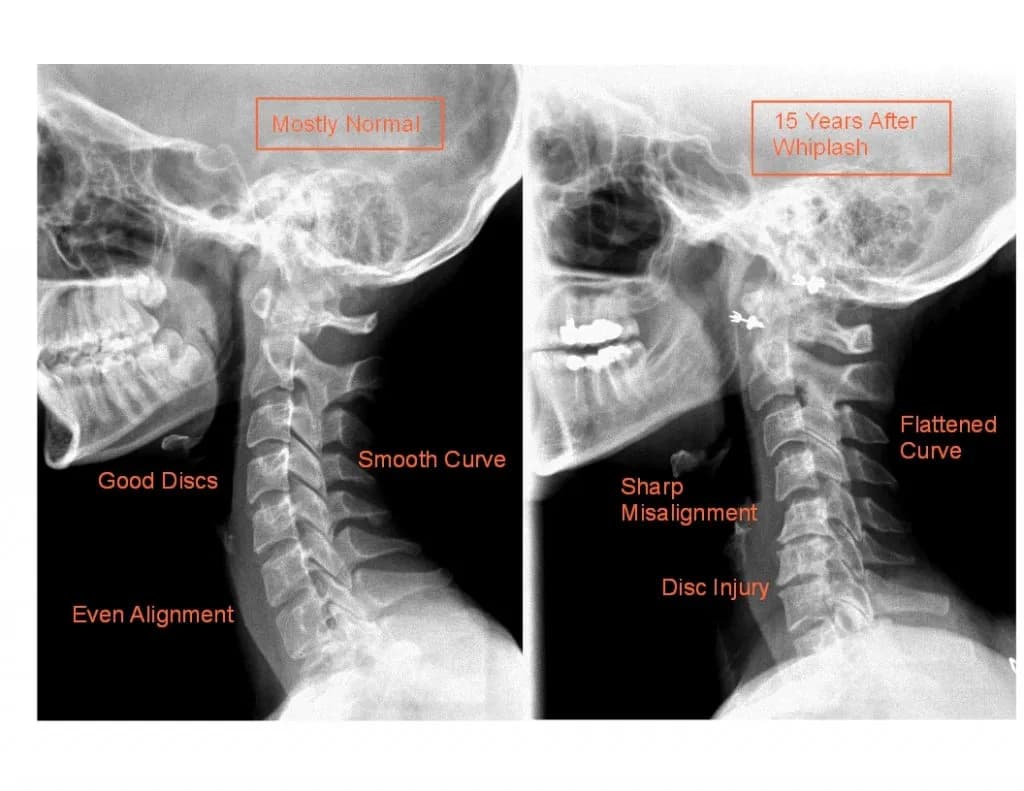

Poznaj objawy bólu kręgosłupa szyjnego, które mogą Cię zaskoczyć. Dowiedz się, kiedy warto skonsultować się z lekarzem i jak dbać o zdrowie szyi.

Poznaj kluczowe objawy neurologiczne przy skręceniu kręgosłupa szyjnego. Dowiedz się, jak je rozpoznać i kiedy szukać pomocy medycznej.